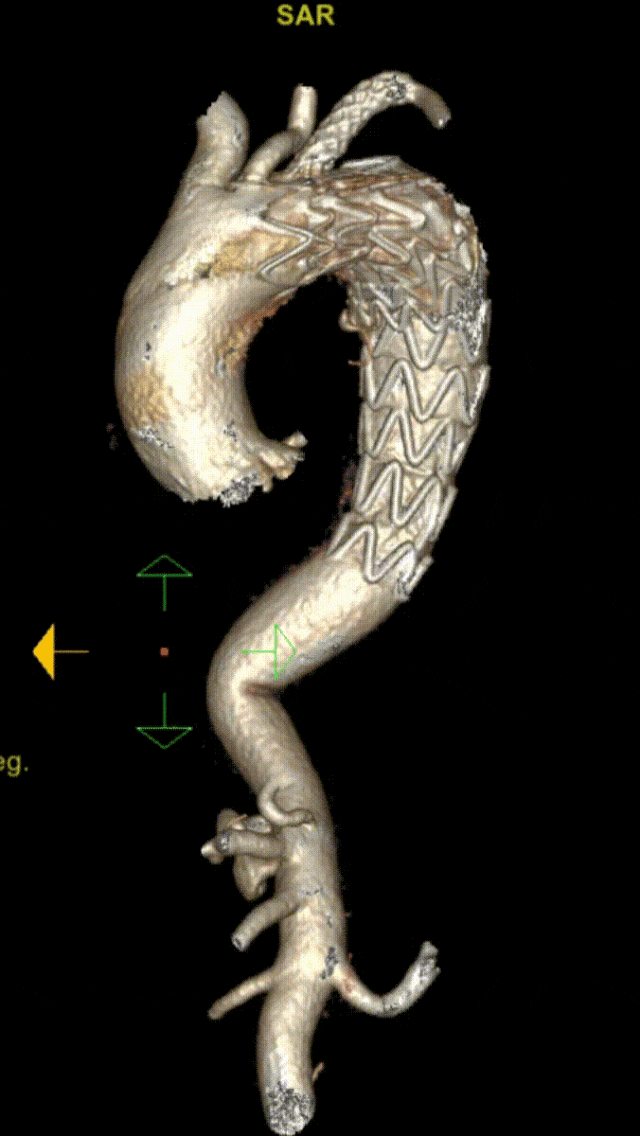

★ 分支支架技术

被视为未来弓上重建的主要方向,有外分支和内分支两种。

Castor单分支支架:中期随访(29个月),106例病例总体技术成功率98.1%,分支通畅率96.2%,再干预率2.8%,死亡率1.9%。

内分支支架:计算流体力学(CFD)分析显示其对血流干扰较外分支明显,但近期疗效相似。外分支支架解剖契合度高,减少血流紊乱和壁面剪切力。